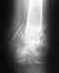

здравствуйте.обращаюсь с огромной надеждой на помощь.мне 36.был отрыв стопы и перелом таранной кости.стопа приживается,а суставу прогнозируют артродез,сейчас нахожусь в стационаре,дело к выписке на случай все-таки замыкания сустава возможно ли избежать этого и сделать эндопротезирование,т.к.для меня блокировка стопы подобно смерти.снимки пока отправить не могу,но обязательно смогу!заранее спасибо,